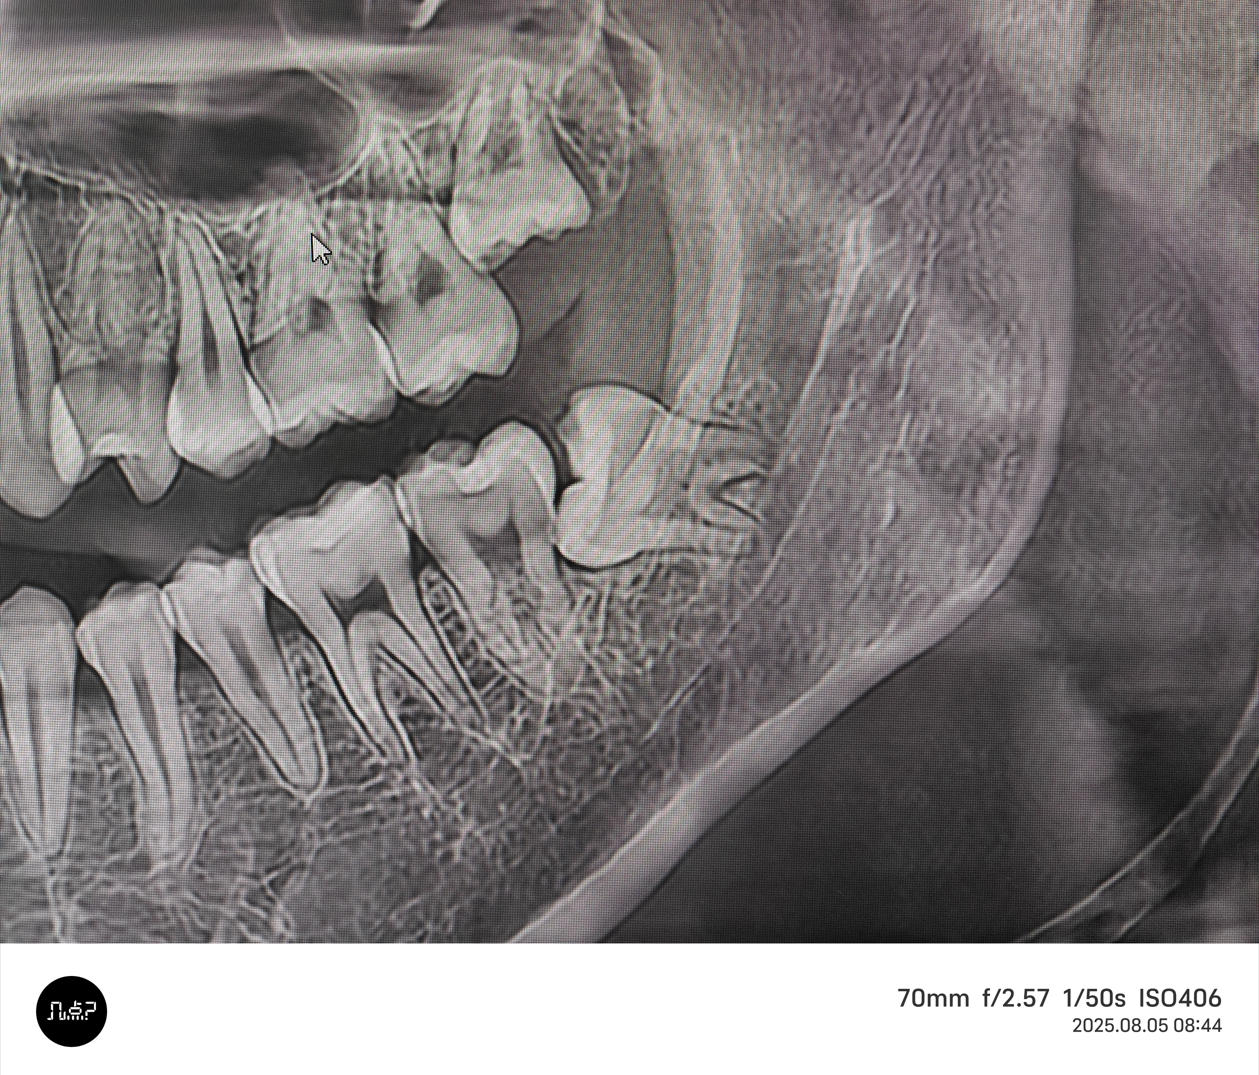

阻生牙拔除

阻生牙拔除 - 案例一

术前 术前

术后 术后